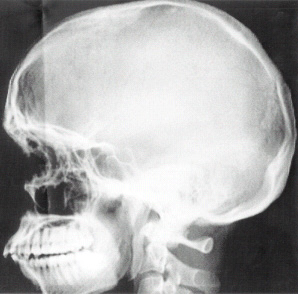

Немного фантазии, чуть-чуть терпения, и получается малодозная цифровая рентгенографическая установка — МЦРУ, которая за несколько секунд позволяет осуществить полное сканирование человека (у меня дома есть электронный снимок моего черепа). Так как мы умеем считать каждый фотон, то полученная за сеанс доза уменьшается по сравнению со стандартной флюорографией почти на два порядка, то есть в сто раз. Если чуть усилить дозу, то можно просвечивать автомобили.